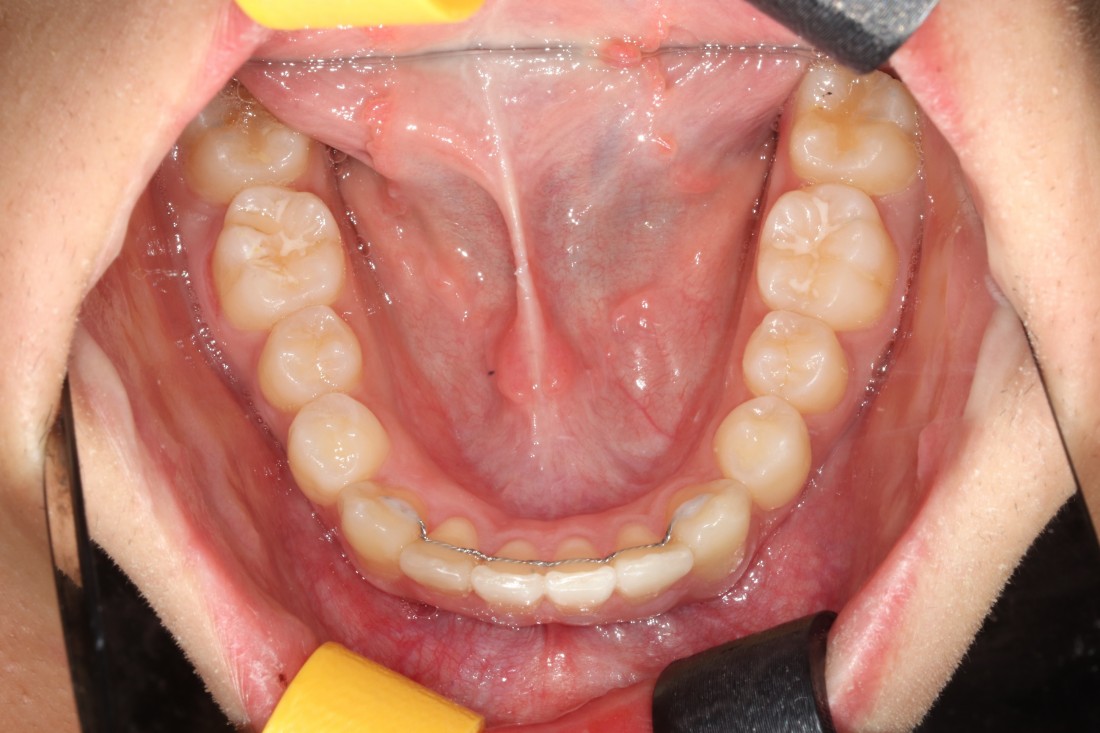

윗니에 아랫니가 거의 덮여있는

과개교합의 경우에는

턱관절 장애를 유발합니다.

윗니가 아랫니를 거의 덮어서

보이지 않을 정도의 부정교합의 종류인데요.